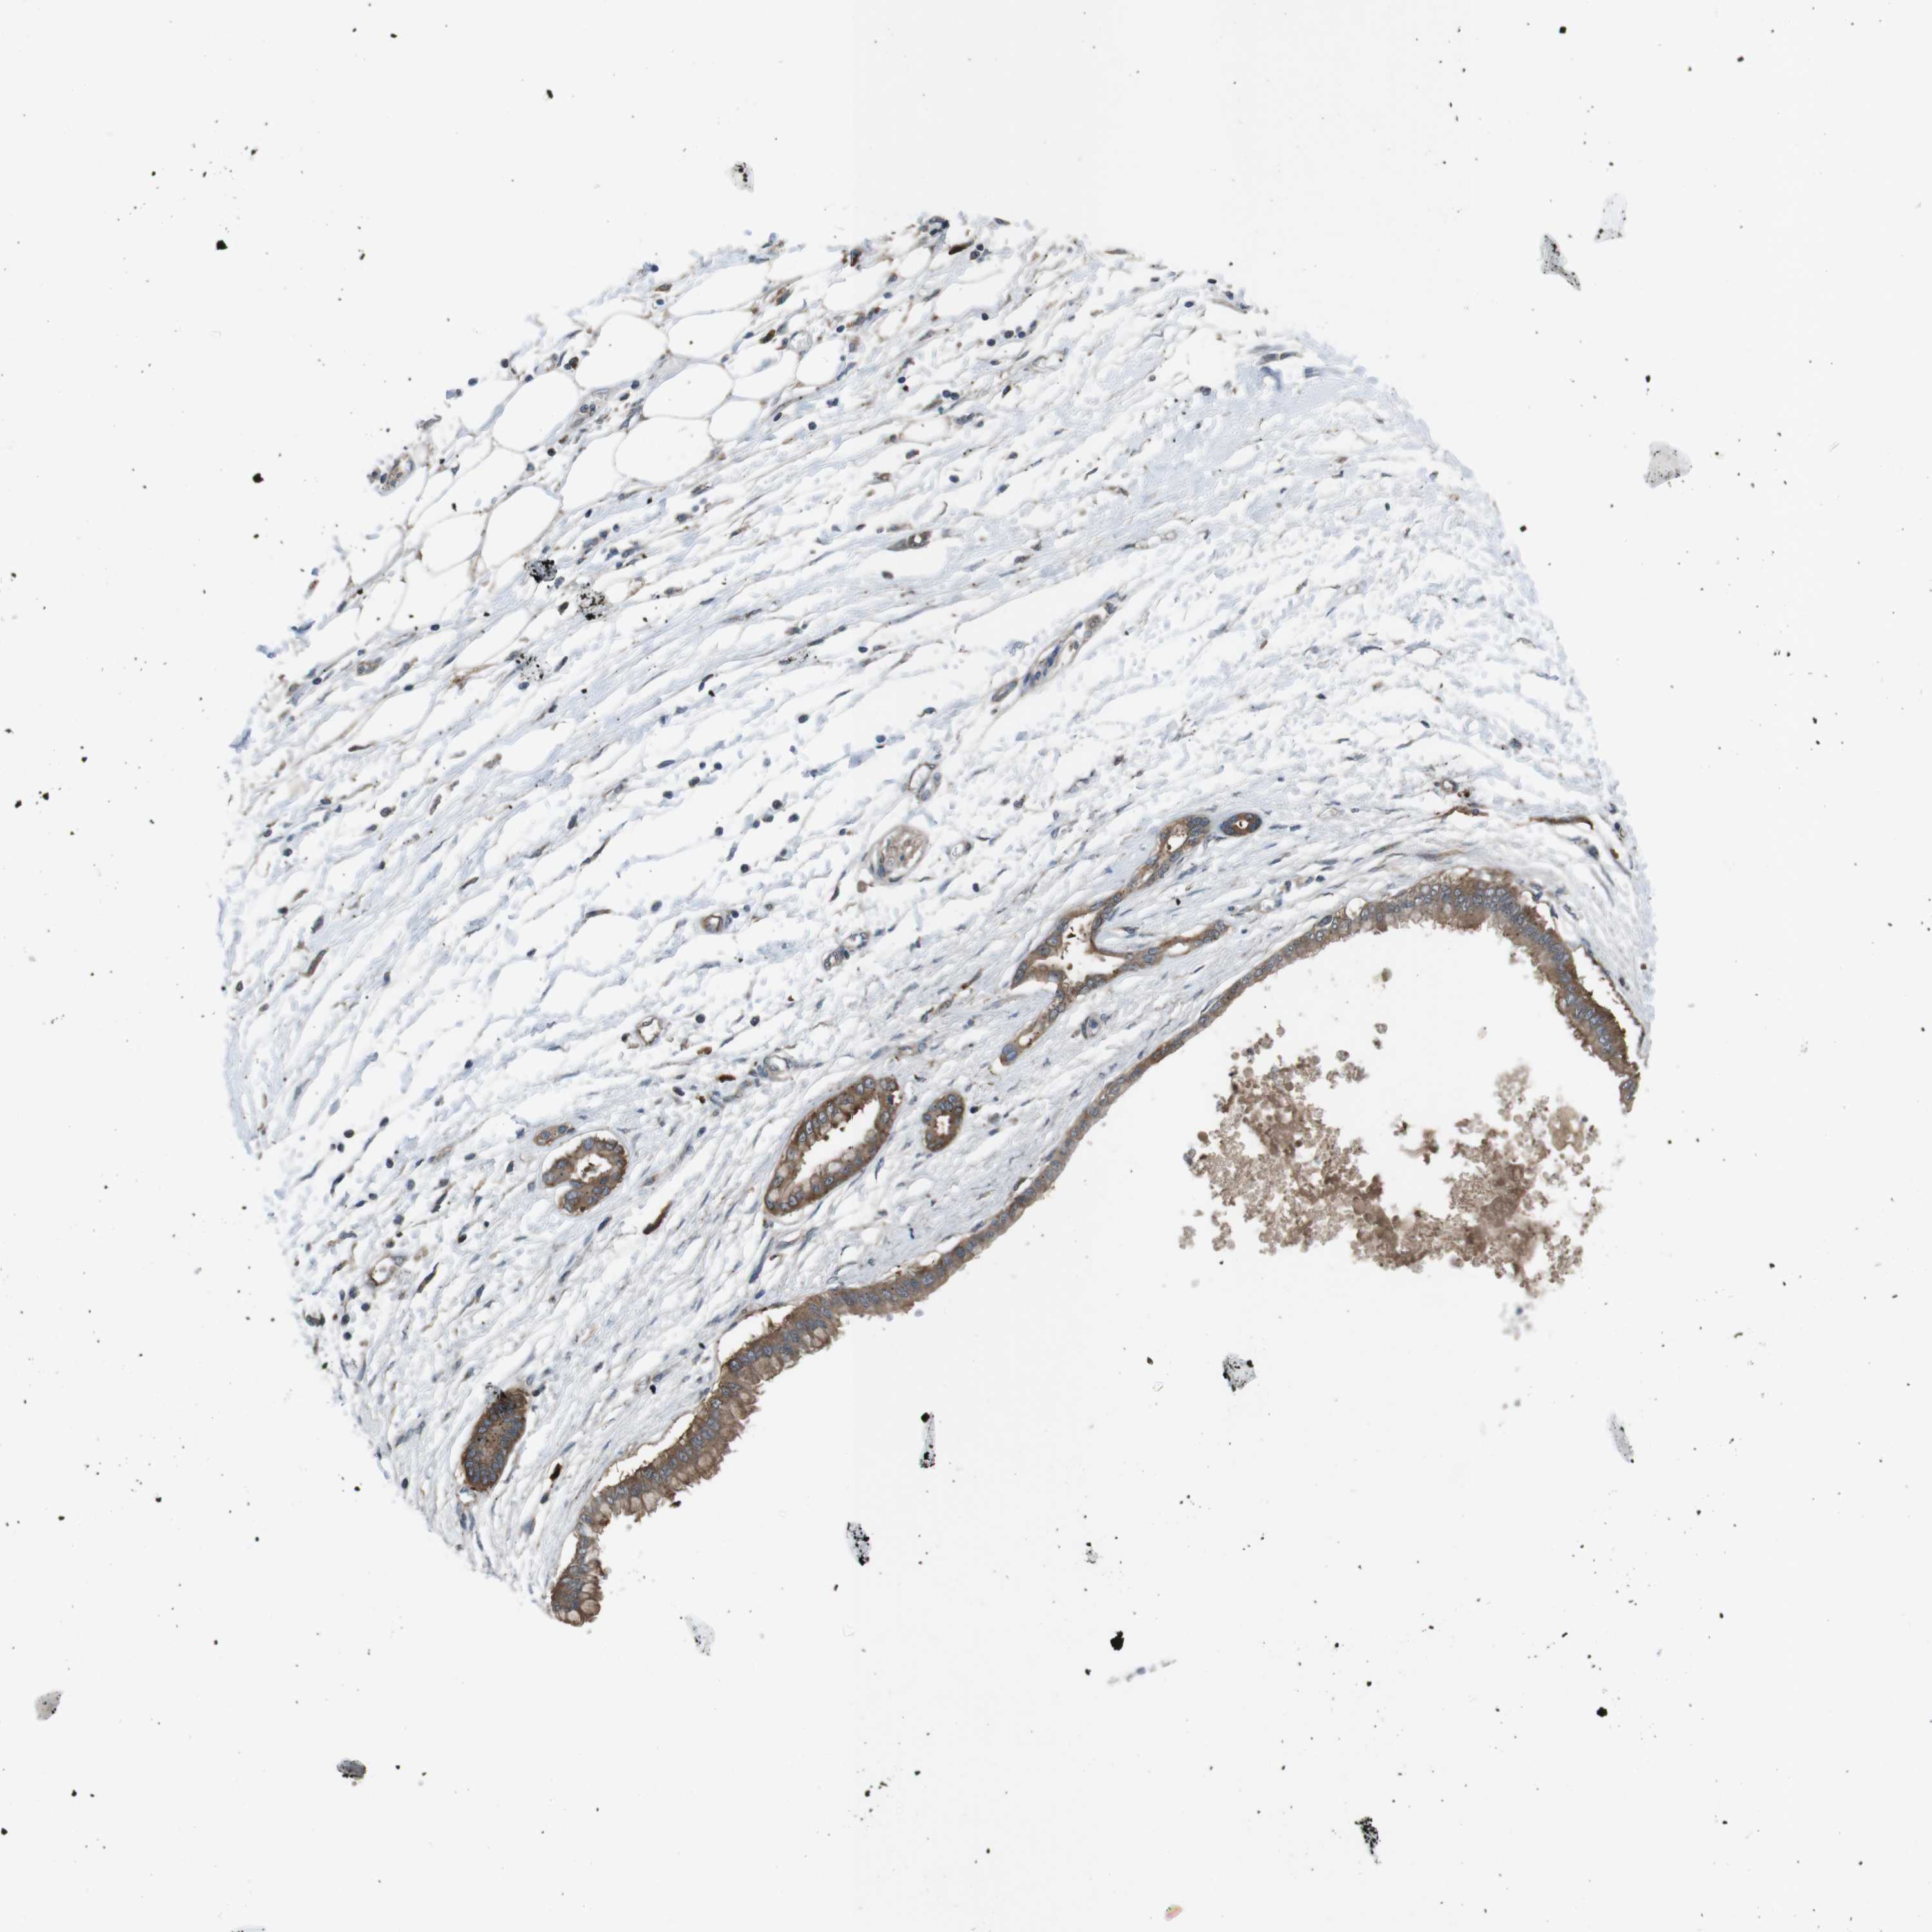

PANCREATIC CANCER - Protein expressioni

A mouse-over function shows sample information and annotation data. Click on an image to view it in a full screen mode. Samples can be filtered based on level of antibody staining by selecting one or several of the following categories: high, medium, low and not detected. The assay and annotation is described here.

Note that samples used for immunohistochemistry by the Human Protein Atlas do not correspond to samples in the TCGA dataset.

Antibody stainingi

Antibody staining in the annotated cell types in the current human tissue is reported as not detected, low, medium, or high, based on conventional immunohistochemistry profiling in selected tissues. This score is based on the combination of the staining intensity and fraction of stained cells.

Each image is clickable and will lead to virtual microscopy that enables deeper exploration of all samples and also displays staining intensity scores, fraction scores and subcellular localization as well as patient and tissue information for each sample.

Antibody HPA014697

Staining

High

Medium

Low

Not detected

Intensity

Strong

Moderate

Weak

Negative

Quantity

>75%

75%-25%

<25%

None

Location

Nuclear

Cytoplasmic/membranous

Cytoplasmic/membranous,nuclear

Adenocarcinoma, NOS